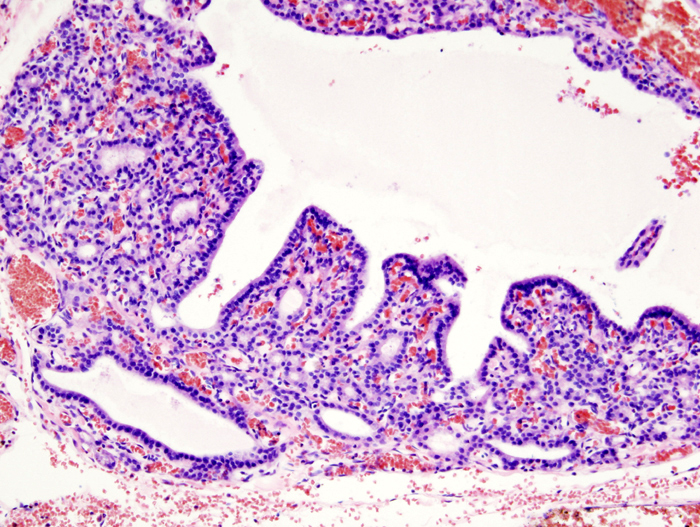

Hyperthyroidism

Hyperthyroidism_(3).jpg